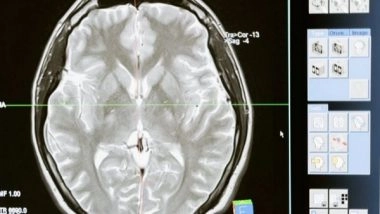

In the study, Li and colleagues performed just such a mapping. They first gathered a set of 1,037 high-quality magnetic resonance imaging (MRI) scans of infants in the third-trimester-to-two-year age interval. The scans came from two other research projects, the UNC/UMN Baby Connectome Project (BCP) and the Developing Human Connectome Project. The team analyzed the scan data using state-of-the-art, computer-based image-processing methods, essentially dividing the cortical surface into a virtual mesh containing thousands of tiny circular areas, and calculating the surface expansion rate for each of these areas.